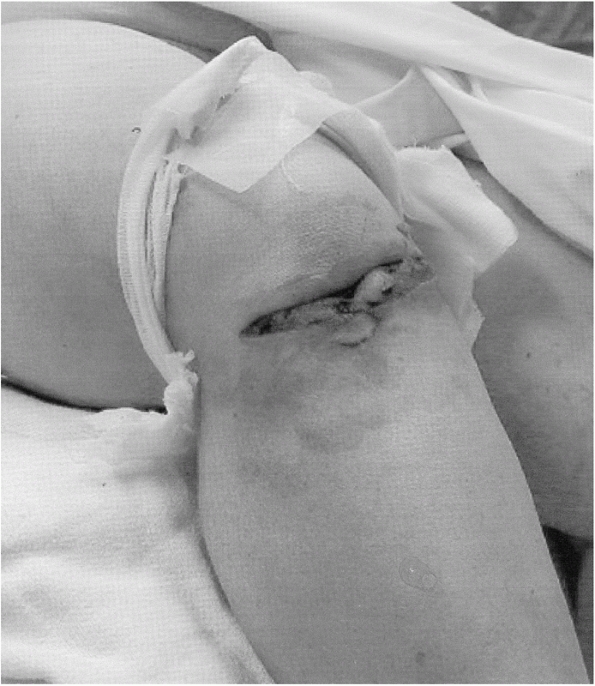

Knee injuries including posterior dislocation, cruciate ligament

dislocations due to direct trauma with the dashboard at impact (Fig. 46-2). Tabuenca et al.169

![]() |

FIGURE 46-2

Photograph of a patient presenting after a dashboard injury. The patient sustained an open knee injury from the incident. The leg is flexed and internally rotated, indicating possible posterior dislocation. |